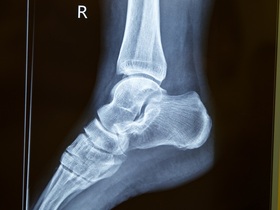

КТ є ефективною діагностикою, коли є підозри на патології черевної порожнини та грудної клітки, захворювання та травми (наприклад, переломи) кісткової тканини, поєднані травми (пошкодження грудного відділу, ребер, хребта, легень та серця), а також різні ускладнення (легеневі ателектази), пневмоторакс і т. п.) та свіжі крововиливи. (КТ легень на хвилі COVID-19 та ускладнень коронавірусної інфекції стала “золотим стандартом” діагностики.) У випадках, коли потрібно досліджувати головний мозок чи м'які тканини, діагностувати пухлину, часто призначають магнітно-резонансну томографію (МРТ).